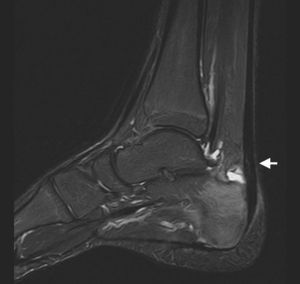

En la radiografía lateral (fig. 1) se apreciaba una prominencia de la tuberosidad posterior del calcáneo, que tras realizar varias mediciones se clasificó como deformidad de Haglund, y una lesión lítica en la cortical de su superficie posterior. En la RM (fig. 2) se visualizó una bursitis retrocalcánea, engrosamiento del tendón aquíleo, con una hiperintensidad de señal lineal intratendinosa en secuencia de supresión grasa, indicativa de rotura parcial, y aumento de intensidad en la región posterior del calcáneo en la misma secuencia, compatible con edema óseo. Estos hallazgos se clasificaron como síndrome de Haglund, diagnóstico que se confirmó quirúrgicamente.

El hallazgo clásico es la tríada tendinitis aquílea, bursitis retrocalcánea y deformidad de Haglund. También se puede apreciar líquido en la bursa retroaquílea. El tendón de Aquiles está engrosado en su inserción y su afectación puede incluir la degeneración mucosa o la rotura parcial. Como tendinitis insercional, no es raro apreciar edema óseo en la región posterior del calcáneo5. Nuestro caso tiene la particularidad de presentar una erosión en la cortical de la región posterosuperior del calcáneo, descrita en casos de bursitis retrocalcánea de largo tiempo de evolución4.